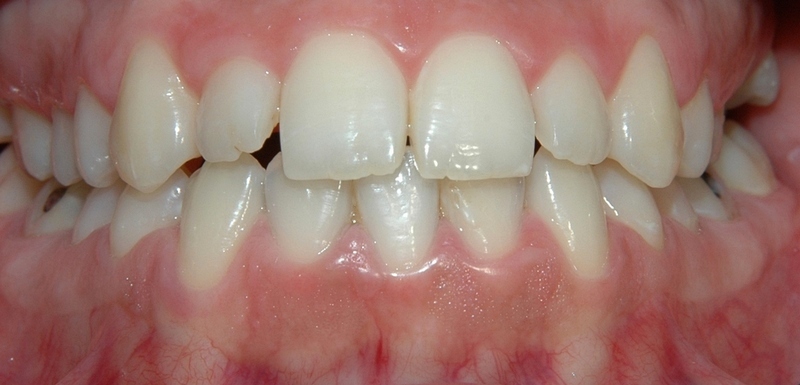

LIJEVO: 1a početno stanje,prednji zubi - DESNO: 1b nakon završetka terapijee LIJEVO: 2a revizija punjenja korijenskih kanala,višekorijenski zubi        <br />

DESNO: 2b nakon završetka terapije LIJEVO: 3a  prije revizije punjenja,jednokorijenski zub<br />

DESNO: 3b  nakon završetka terapije LIJEVO: 4a liječenje granuloma ,početno stanje<br />